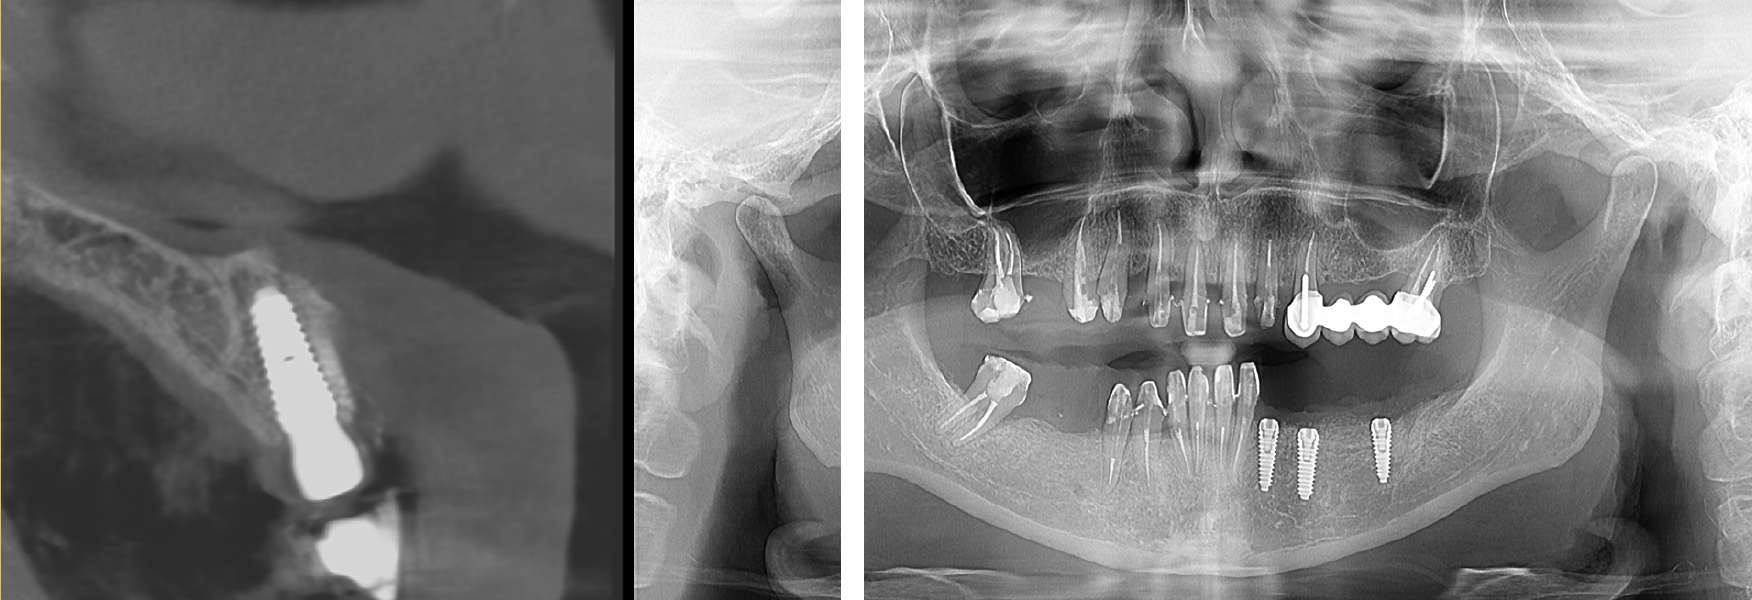

Postoperator se va evalua corectitudinea poziției implanturilor cu ajutorul investigațiilor imagistice (Fig. 7.5.4).